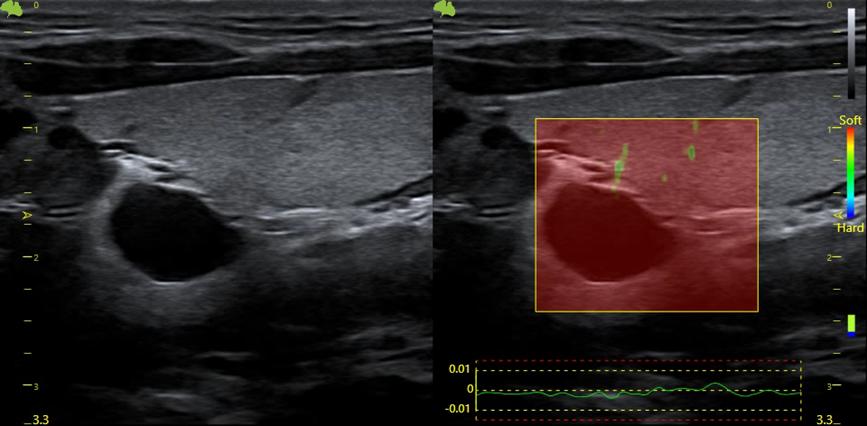

5. Giải pháp hình ảnh tổng quát: EI (Hình ảnh đàn hồi mô nén)

Một kỹ thuật không xâm lấn, thời gian thực đo độ cứng của mô để phát hiện sớm các dấu hiệu ung thư, giảm số lượng sinh thiết và theo dõi xơ hóa trong bệnh gan mãn tính. Kỹ thuật này đặc biệt hữu ích cho việc đánh giá vú, gan, tuyến giáp, tuyến tiền liệt và hệ cơ xương khớp.

Công nghệ đàn hồi mô trên Vinno